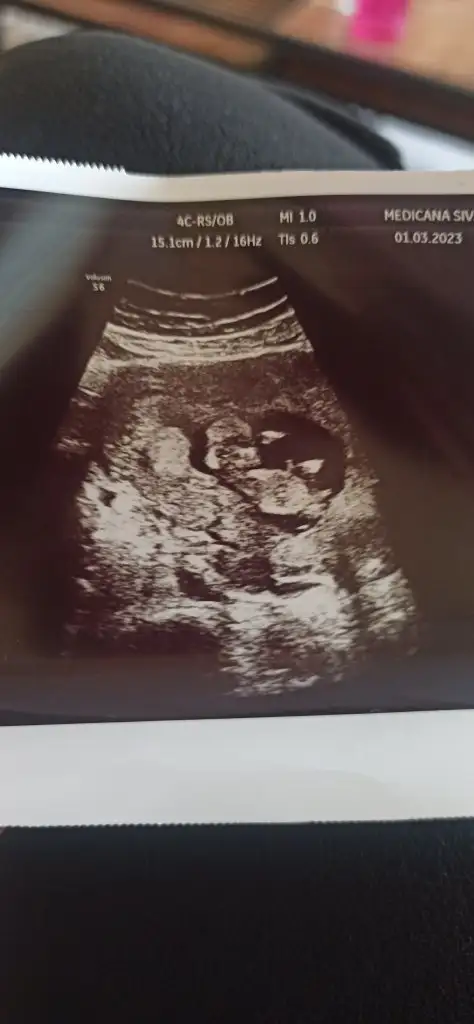

Merhaba kizlar 13+2 deyiz bize de cinsyet tahmini yapabilirmisiniz 🥰

IMG_20230301_114200.webp